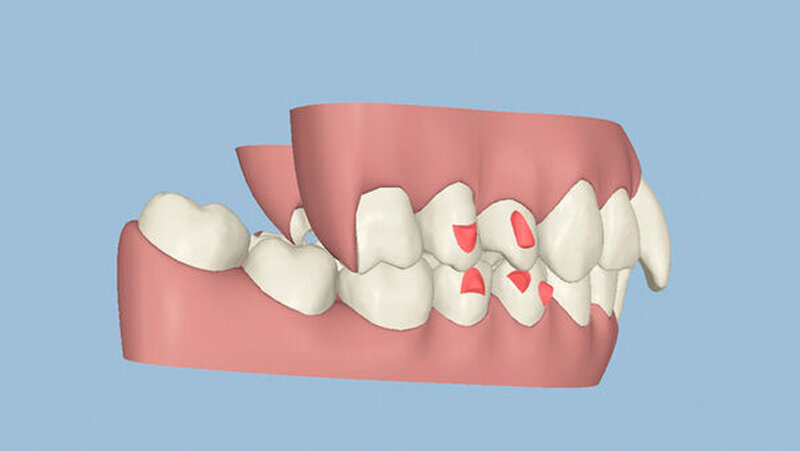

Die Sulkustiefen konnten auf etwas weniger als 4 mm reduziert werden, während der Blutungs- und Plaque-Index bei weniger als 15 Prozent lag. Daher wurde eine kieferorthopädische Behandlung über die nächsten zwei Jahre in Kombination mit engen zahnärztlichen Kontrollen geplant. Als Mittel der Wahl entschieden wir uns gemeinsam mit dem Patienten für das Invisalign-System, da hiermit sowohl eine Schienung als auch eine kraft-arme Bewegung der Zähne möglich sein sollte. Für den Frontzahnbereich wurden keine Attachments geplant, so dass hier eine unnötige Hebelwirkung umgangen werden konnte (Abbildung 3).

Um einen kompletten Lückenschluss im Oberkiefer zu ermöglichen, musste im Unterkieferfrontzahnbereich zusätzlich zur Derotation und Positionierung der Zähne – insbesondere Zahn 41 – von approximaler Schmelzreduktion, kurz ASR , Gebrauch gemacht werden, um einer Tonn`schen Diskrepanz entgegenzuwirken (siehe dazu Abbildung 7 auf Seite xy).